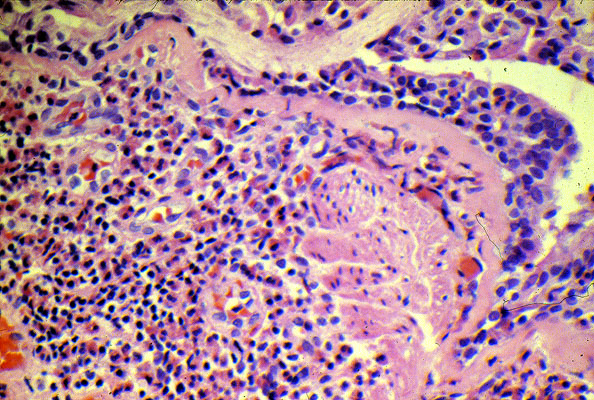

Bronchial

asthma

, higher power. Notice inflammatory cells composed of lymphocytes and many eosinophils. There is prominent thickening of the basement membrane.